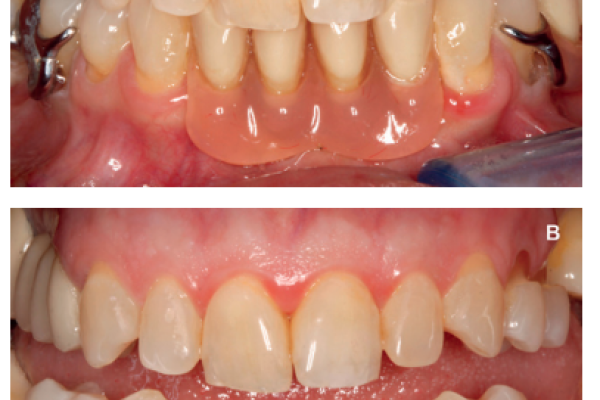

7 | CLINICAL CASE | DIGITAL FLOW IN UNITARY DENTAL IMPLANTS REHABILITATION IN ANTERIOR SECTOR. URGICAL AND PROSTHETIC PLANNING. CASE REPORT |